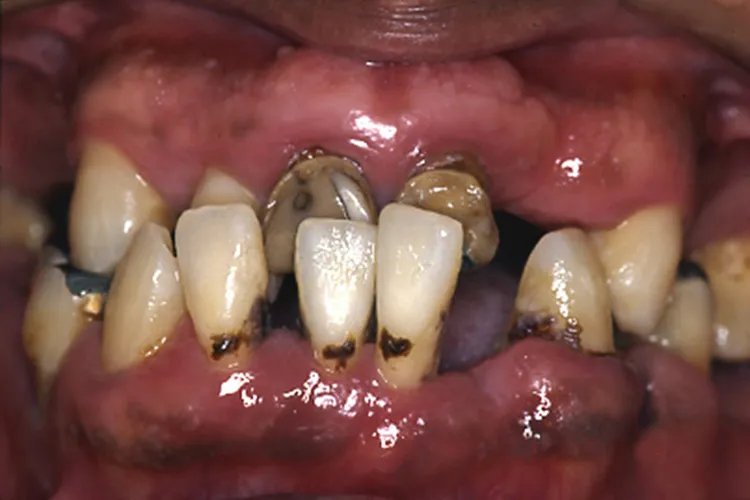

牙周炎图片

的有关信息介绍如下:概述牙周炎多表现为牙龈红肿,刷牙时易出血,严重时形成牙周袋,甚至牙齿出现松动移位。牙周炎可能与牙菌斑、牙石、食物嵌塞、解剖因素、口腔不良习惯等原因有关。症状牙周炎分类尚不成熟,主要包括慢性牙周炎、侵袭性牙周炎和伴有全身疾病的牙周炎。各种牙周炎的临床表现相似,常见症状有牙龈红肿、刷牙时易出血、牙龈退缩、口腔异味、咬合不适或疼痛、牙松动等。牙周炎严重时可导致牙周组织破坏,形成牙周袋,造成附着丧失和牙槽骨吸收。晚期当牙周组织破坏到一定程度,牙发生松动移位甚至脱落。其间可因牙周膜炎症出现咬合无力、不适或疼痛。常出现一系列伴发病变,如牙龈退缩、牙根暴露、根分叉病变、食物嵌塞、牙根面敏感、根面龋、牙周脓肿、逆行性牙髓炎等。